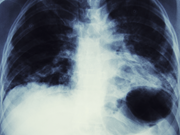

Røntgenbilde av pasient med lungekreft. Dette er den kreftformen som tar flest liv i Norge. Forskere ved SINTEF har nå utviklet en nanomedisin som viser svært lovende resultater. Foto:...